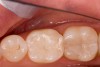

Figure 5